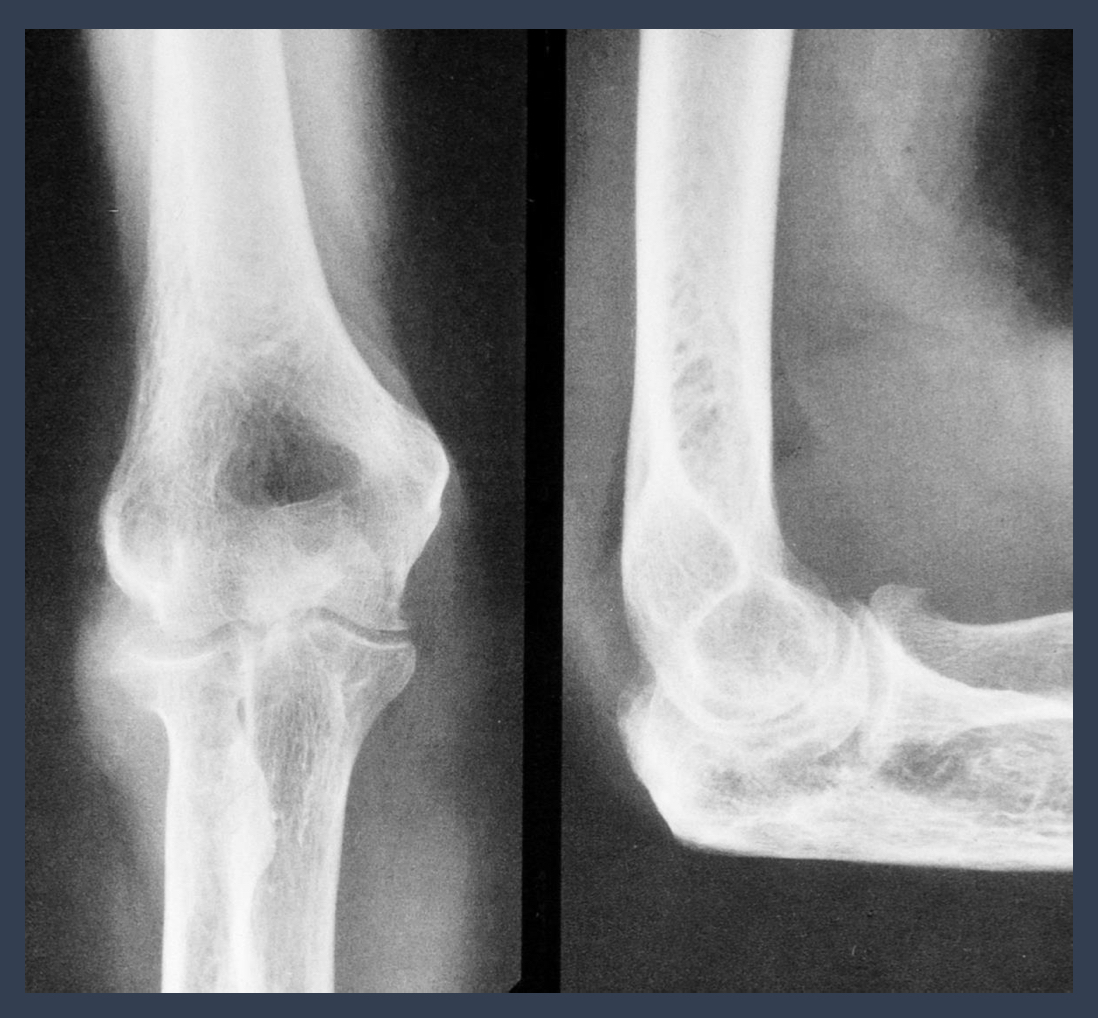

what do you think this is?

septic arthritis

NOTE: upper extremity is uncommon

what is noted here?

what condition is this?